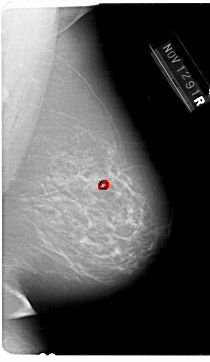

A_1648_1.RIGHT_MLO

RIGHT_MLO LINES 6871 PIXELS_PER_LINE 3976 BITS_PER_PIXEL 12 RESOLUTION 43.5 OVERLAY

FILE: A_1648_1.RIGHT_MLO.OVERLAY

TOTAL_ABNORMALITIES 1

ABNORMALITY 1

LESION_TYPE CALCIFICATION TYPE PLEOMORPHIC DISTRIBUTION CLUSTERED

ASSESSMENT 4

SUBTLETY 2

PATHOLOGY BENIGN

TOTAL_OUTLINES 1

BOUNDARY